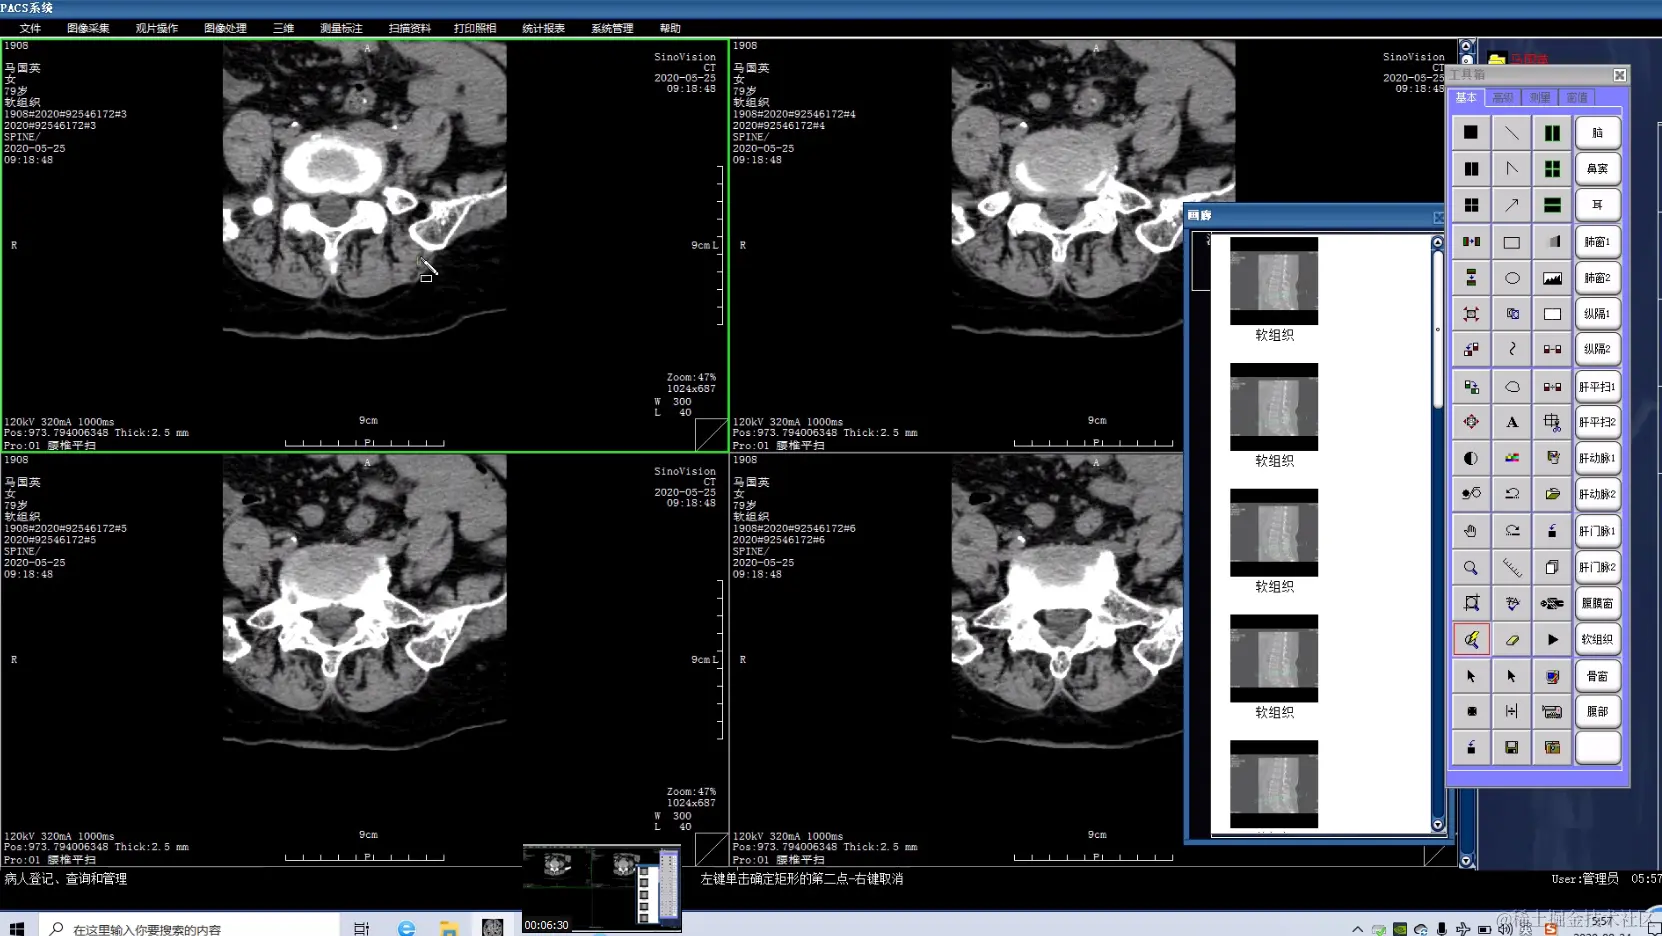

运维级医院PACS系统有源码,有演示,带使用手册和操作说明书 ,开发环境:VC + MSSQL

PACS系统可实现检查预约、病人信息登记、计算机阅片、电子报告书写、胶片打印、报表统计、数据备份等一系列满足影像科室日常工作的功能,并且由于影像数字化存储,用户可利用影像处理与测量技术辅助诊断、方便快捷地查找资料或利用网络将资料传输至临床科室,还可与医院HIS、LIS无缝连接。集成专业三维影像后处理功能,包括:三维多平面重建、三维容积重建、三维表面重建、三维虚拟内窥镜、最大/小密度投影、心脏动脉钙化分析等。